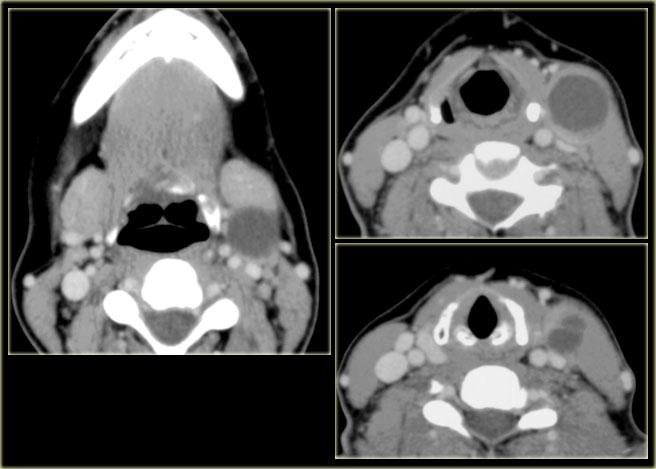

U lympho

Bước 1: Xác định khoang

Bên trái là hình ảnh một bệnh nhân có sưng nề hai bên cổ.

Hình ảnh CT tại mức xương móng cho thấy nhiều tổn thương dạng tròn nằm ở phía trong cơ ức đòn chũm và phía sau tĩnh mạch cảnh trong.

Các tổn thương đa ổ hai bên này được xác định nằm trong khoang cổ sau.

Bước 2

Phân tích các thành phần giải phẫu bình thường của khoang cổ sau:

- Mô mỡ

Mô mỡ có hình ảnh bình thường. - Thần kinh phụ

Bệnh lý thần kinh phụ thường biểu hiện một bên. - Đám rối thần kinh cánh tay

Có thể cân nhắc các bệnh lý đám rối thần kinh cánh tay như u xơ thần kinh.

Tuy nhiên, chúng ta sẽ kỳ vọng thấy các tổn thương liên tục dọc theo đường đi của dây thần kinh, chứ không phải các tổn thương tròn riêng biệt như thế này. - Túi bạch huyết phôi thai nguyên thủy:

Các di tích bẩm sinh như u nang bạch huyết (cystic hygroma) có thể xuất hiện hai bên.

Đây là các tổn thương nang hợp lưu có giảm tỷ trọng.

Bước 3

Bằng phương pháp loại trừ, chúng ta có thể kết luận đây là các hạch bạch huyết to hai bên với hình ảnh ngấm thuốc đồng nhất.

Ngấm thuốc đồng nhất là đặc điểm điển hình của u lympho.

Hoại tử trung tâm đặc trưng hơn cho di căn hạch từ ung thư biểu mô tế bào vảy.

Sinh thiết hạch bạch huyết ở bệnh nhân này xác nhận chẩn đoán u lympho không Hodgkin tế bào B.